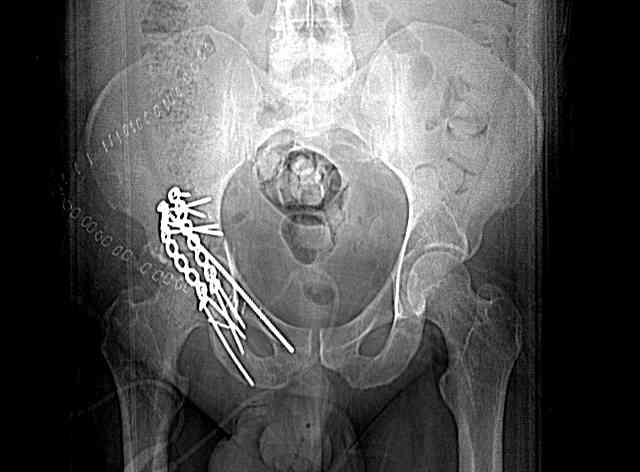

45 yo male in MVA, only other injury=small subarrachnoid bleed (neurologically fine, GCS never <14), with this transverse & associated posterior wall fx-dislocation 7/7

In skeletal traction thru distal femoral pin 40 lbs with decent reduction - except for the free fragments in the hip joint. ORIF planned for post-injury day 11.

Stabilize anterior column with fluoroscopically guided screw across this end of the transverse fx - As usual, after your reduction of the femoral head, the transverse fx became minimally displaced - slightly gapped without stepoff. I usually (reduce &) stabilize the medial side of the posterior column (transverse fx) with a short plate - before placing the anterior screw unless the transverse fx is undisplaced.

Biggest problem appears to be impaction & comminution of the posterior wall fx site - you've left out some CT cuts. This is not just fragments in joint. It may leave a deficient area, &/or block satisfactory posterior wall reduction.